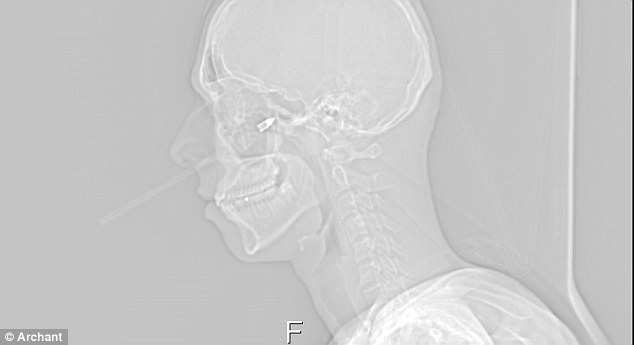

X光片顯示,這支箭插入塔維尼右臉內(nèi)7厘米多深

醫(yī)生檢查后發(fā)現(xiàn),這支箭射入塔維尼的右側(cè)面頰足足3英寸(約合7.6厘米)深,致使他面部肌肉和臉頰骨受損,幸運(yùn)的是并未傷及要害。醫(yī)生稱,這支箭如果再靠上2毫米就會傷及動脈而致命,而如果位置再靠下一些塔維尼將會喪失說話的能力。